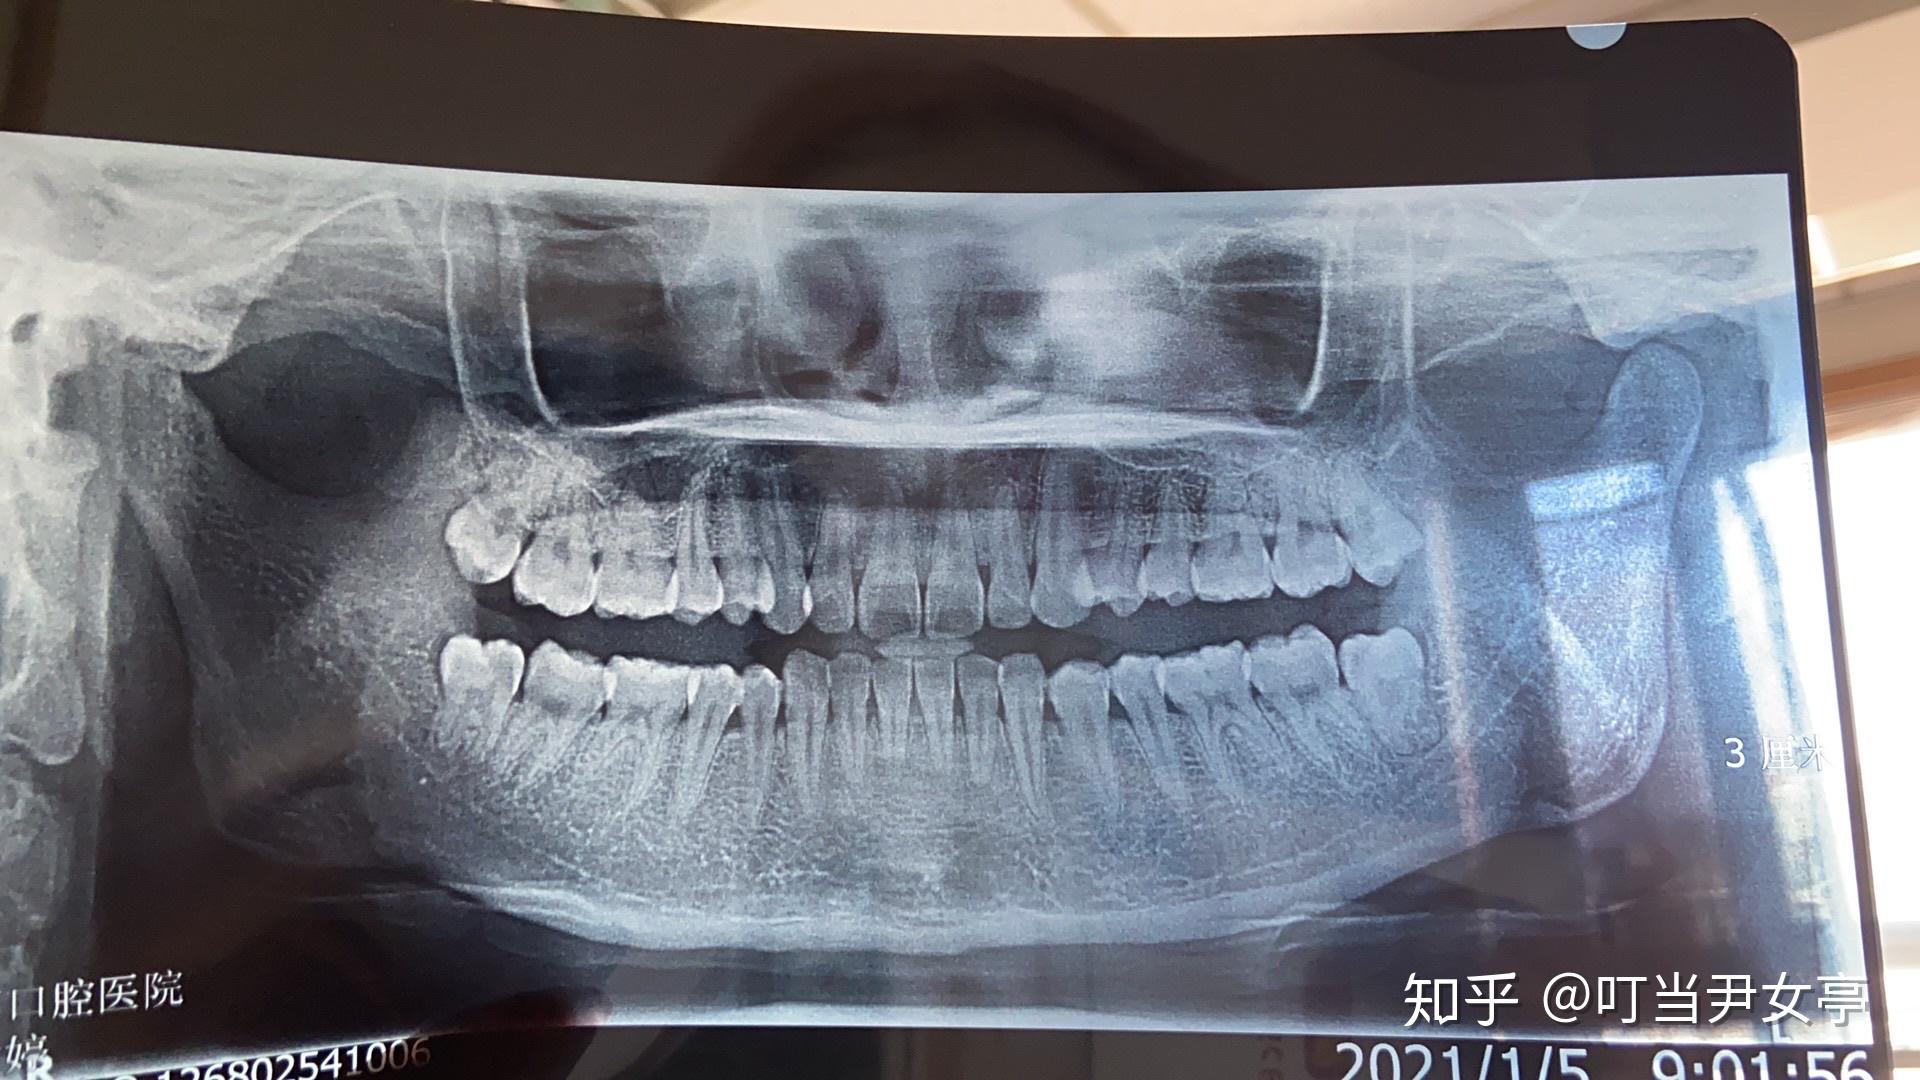

牙齿ct怎么看全景? - 知乎

全景牙片在线求解

今年22岁,这是我在医院拍的牙的全景图,还没开始治